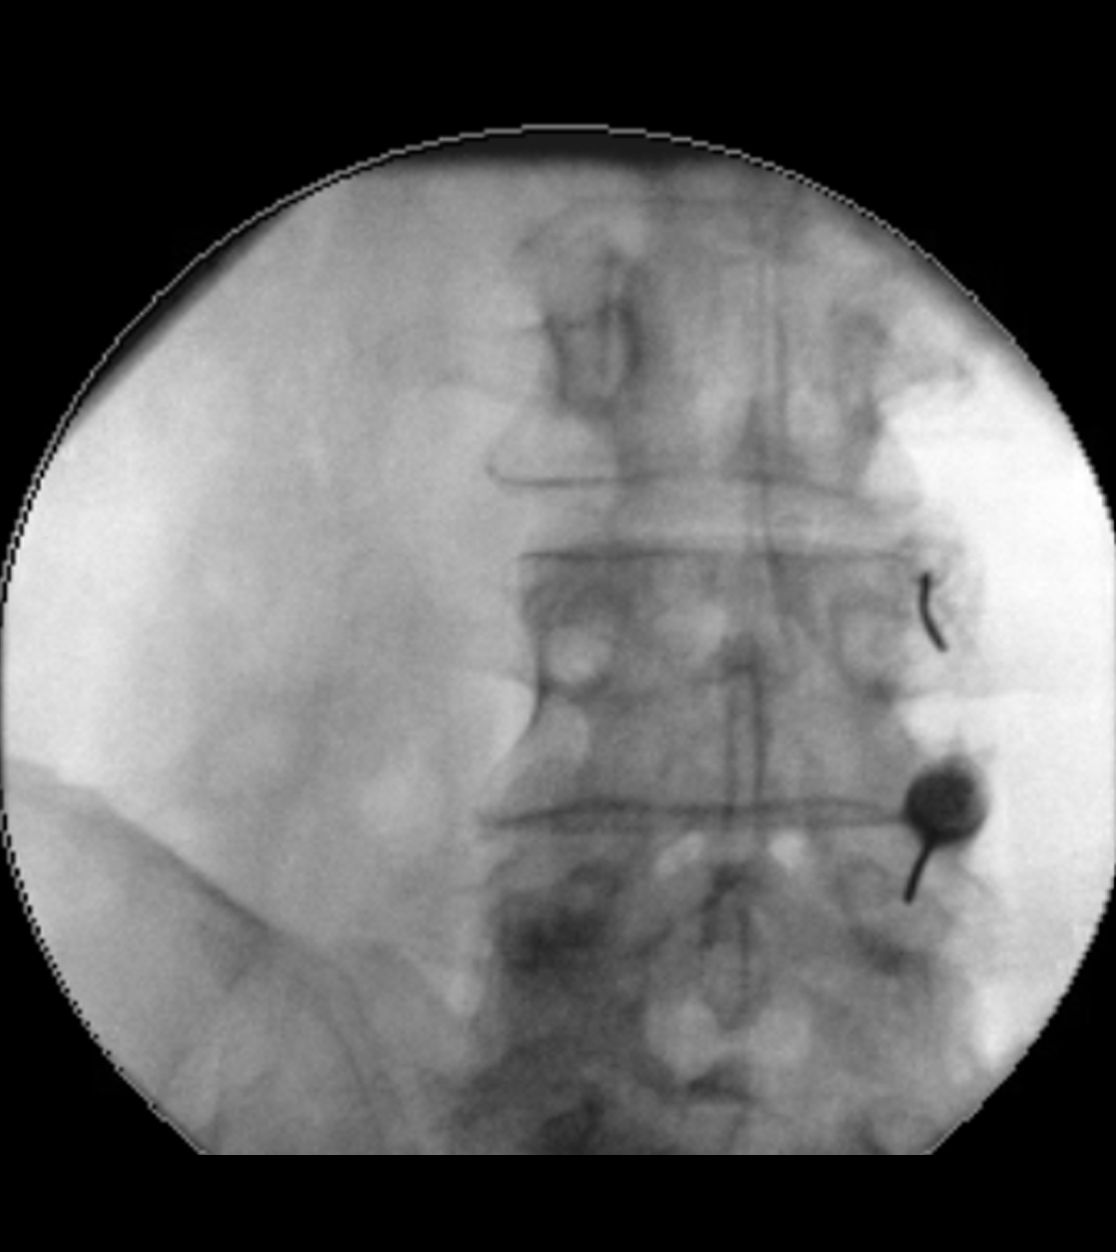

Bei der Rückenmarkstimulation wird in der Wirbelsäule eine Elektrode platziert. Über diese werden elektrische Impulse an das Rückenmark abgegeben. Die Elektrode ist mit einem Impulsgeber (vergleichbar mit einem Herzschrittmacher) verbunden. Das operative Verfahren gliedert sich in zwei Abschnitte: Im ersten Eingriff erfolgt, unter örtlicher Betäubung und Röntgenkontrolle, die Platzierung der Elektrode im Rückenmarkskanal. Im Anschluss erfolgt eine Testphase. Ziel ist es, die Abdeckung des Schmerzareals durch die Stimulation und die daraus resultierende Schmerzreduktion zu testen. Bei zufriedenstellendem Ergebnis wird in einem zweiten Eingriff der Impulsgeber unter die Haut implantiert.

Röntgenbild zur Rückenmarkstimulation

Röntgen-gestützte Infiltrationen stellen eine präzise und schonende Methode zur Behandlung von Rücken- und Gelenkschmerzen dar. Durch den Einsatz von Röntgenbildwandlern wird die genaue Position der Nadel während des Eingriffs sichtbar gemacht, wodurch eine präzise und zielgerichtete Behandlung möglich ist. Zielgebiete der Infiltration sind hierbei die sog. Facettengelenke oder das Ileosakralgelenk (ISG). Wenn die infiltrative Methode nicht ausreicht bzw. die Schmerzlinderung nur kurz anhält, setzen wir auch Facettenthermokoagulationen ein, bei denen durch gezielte Wärmeanwendungen an den betroffenen Nerven die Schmerzübertragung blockiert wird.

Infiltration eines Ileosakralgelenks